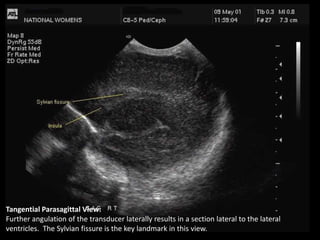

Tangential Parasagittal View:

Further angulation of the transducer laterally results in a section lateral to the lateral

ventricles. The Sylvian fissure is the key landmark in this view.

Tangential Parasagittal View: Furtherangulation of the transducer laterally results in a section lateral to the lateral ventricles. The Sylvian fissure is the key landmark in this view.